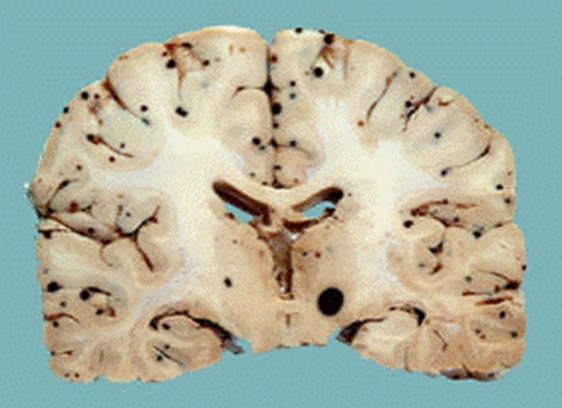

Black dots at gray white junction probably a hemorrhagic met

Hemorrhagic I think this one was melanoma mets

Brain mets

Bottom cerebellum loaded with mets can be silent